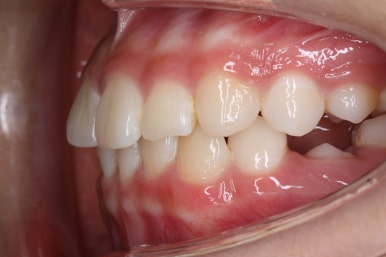

부산치아교정잘하는곳 처음 오셨을 때의 입안 모습입니다.

맨 우측 밑에 사진을 보시면 이가 하나 더 나와야 할 자리에(화살표) 앞뒤로 치아가 쓰러지면서 자리를 거의 없애버렸습니다.

따라서 이가 나올래야 나올 수가 없는 상태였습니다.

왼쪽 맨 위 사진을 보시면 아래 치열의 중앙이 한 쪽으로 쏠린 것을 알 수 있는데요. 역시 치아가 나올 자리가 없어지면서 치열이 쏠러버렸다는 것을 알 수 있습니다.